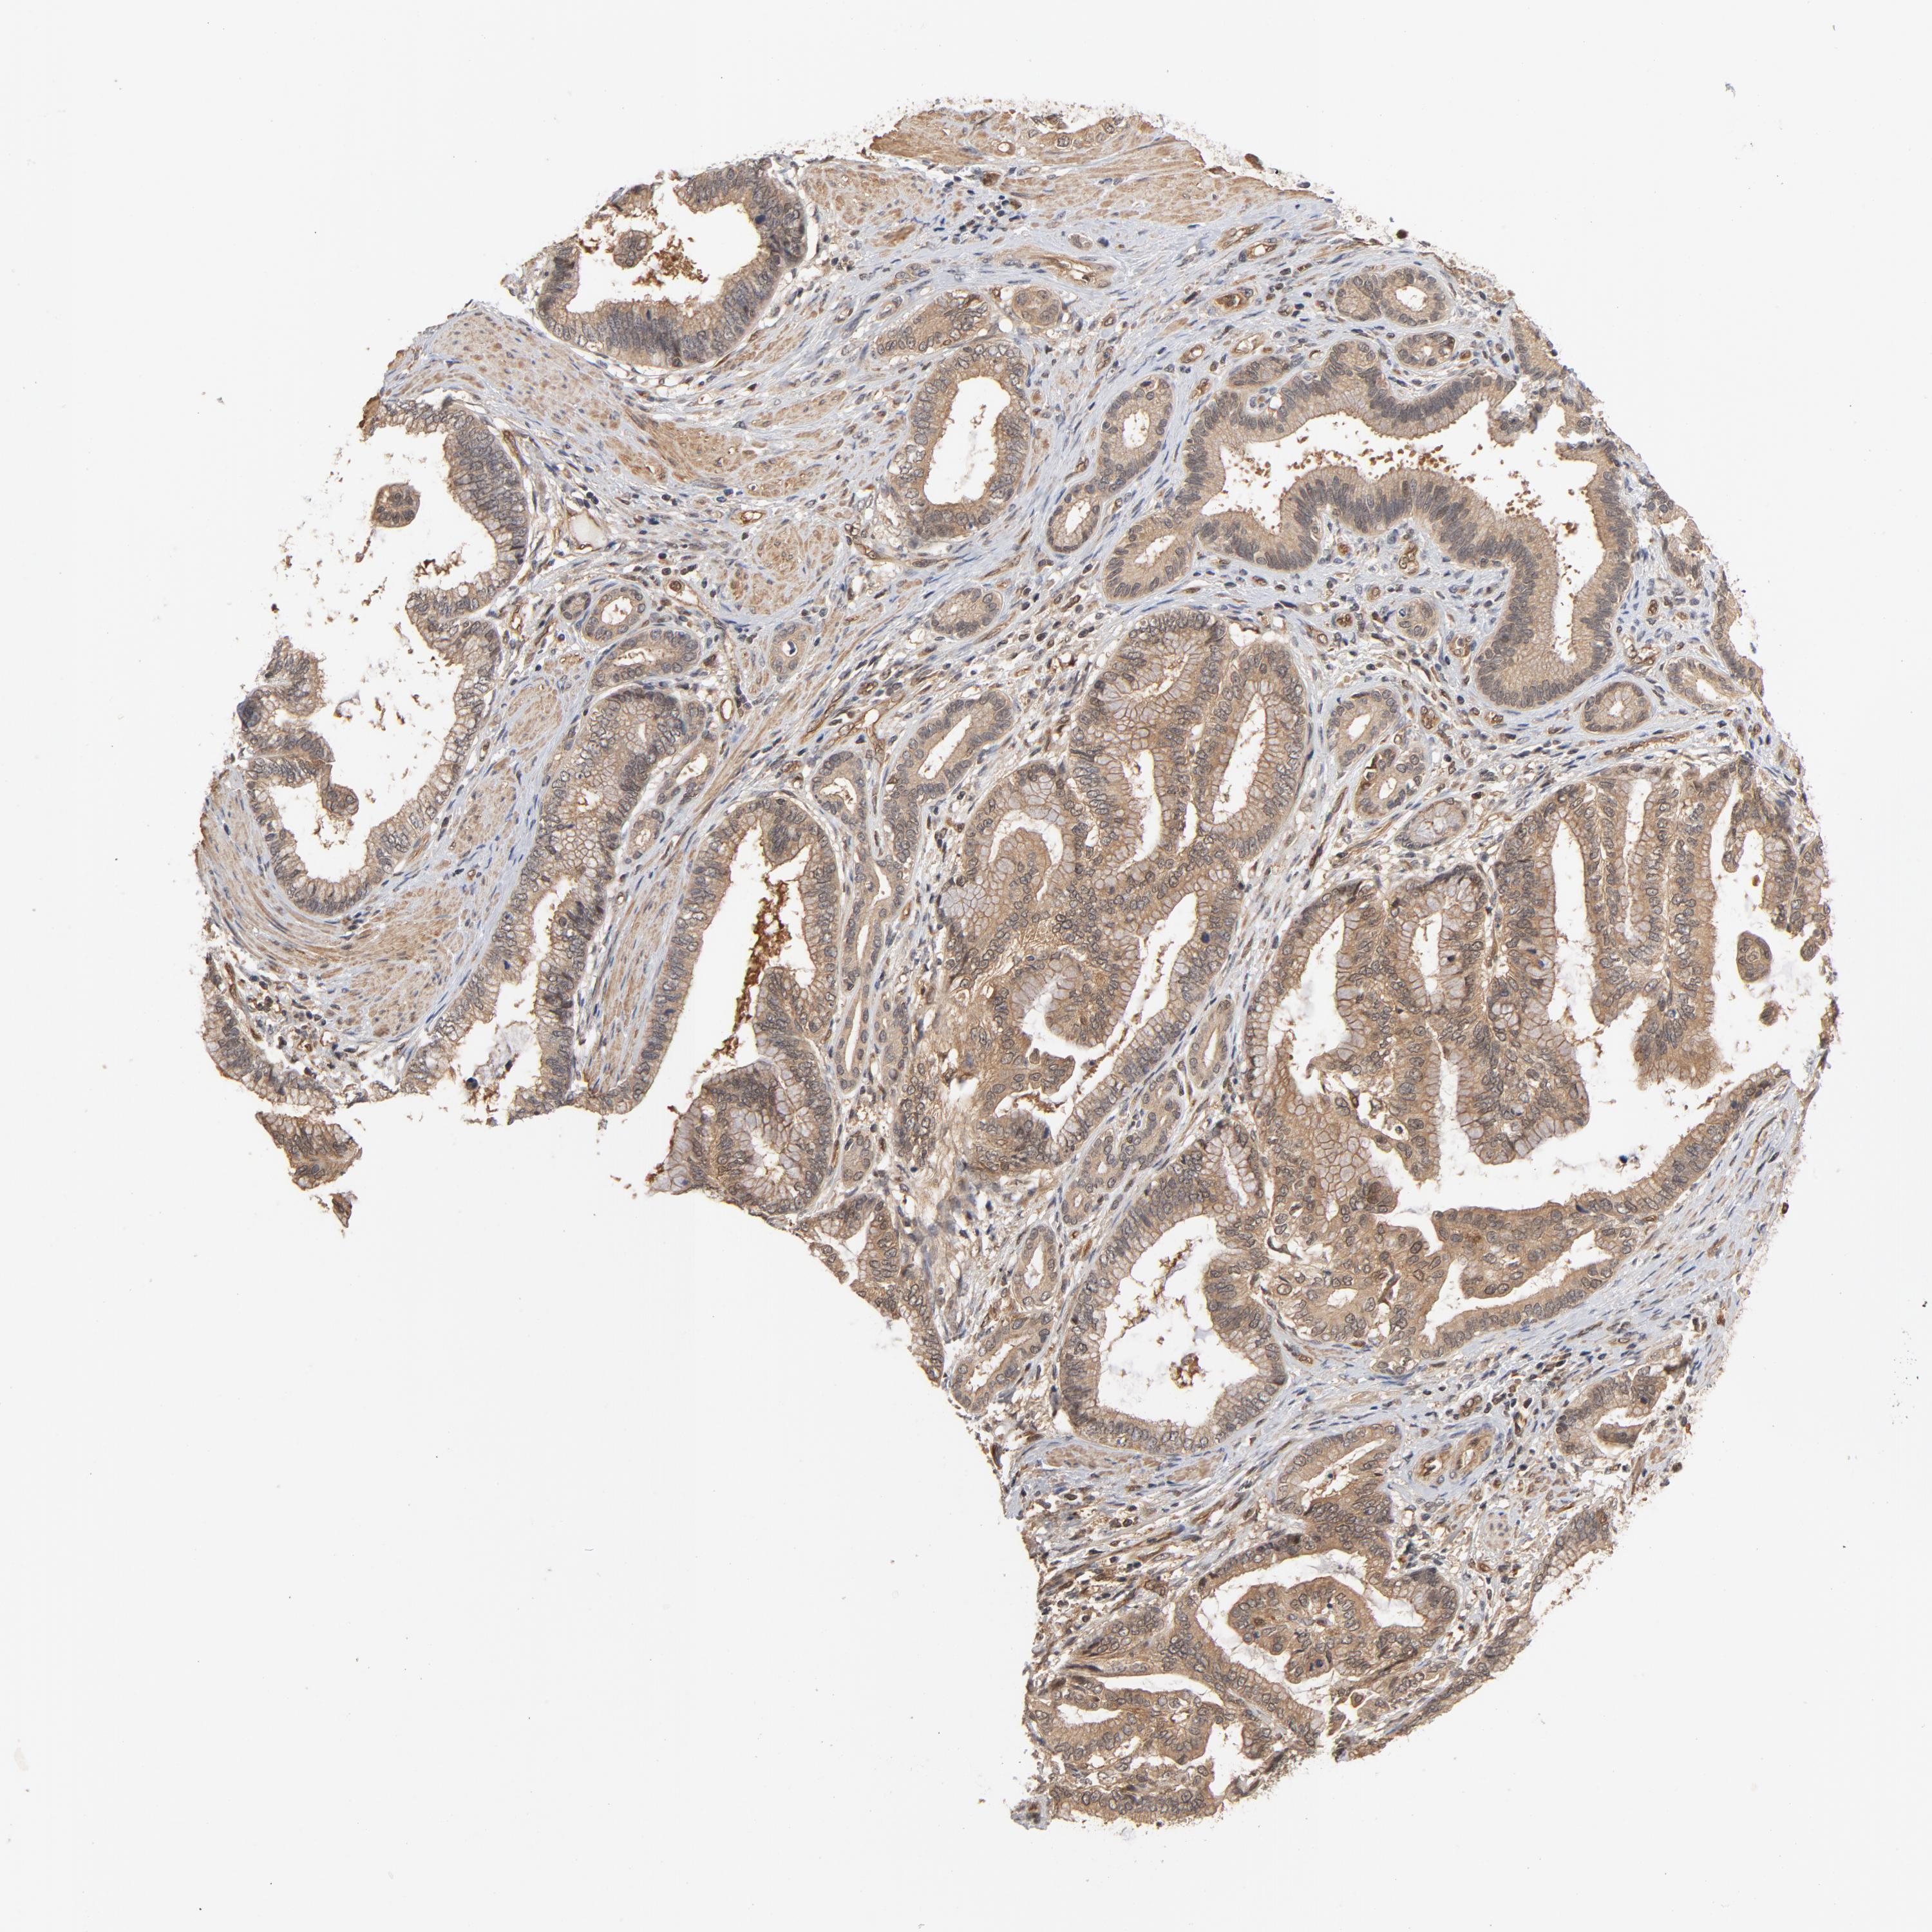

PANCREATIC CANCER - Protein expressioni

A mouse-over function shows sample information and annotation data. Click on an image to view it in a full screen mode. Samples can be filtered based on level of antibody staining by selecting one or several of the following categories: high, medium, low and not detected. The assay and annotation is described here.

Note that samples used for immunohistochemistry by the Human Protein Atlas do not correspond to samples in the TCGA dataset.

Antibody stainingi

Antibody staining in the annotated cell types in the current human tissue is reported as not detected, low, medium, or high, based on conventional immunohistochemistry profiling in selected tissues. This score is based on the combination of the staining intensity and fraction of stained cells.

Each image is clickable and will lead to virtual microscopy that enables deeper exploration of all samples and also displays staining intensity scores, fraction scores and subcellular localization as well as patient and tissue information for each sample.

Antibody HPA003928

Antibody CAB004214

Adenocarcinoma, NOS

Adenocarcinoma, metastatic, NOS